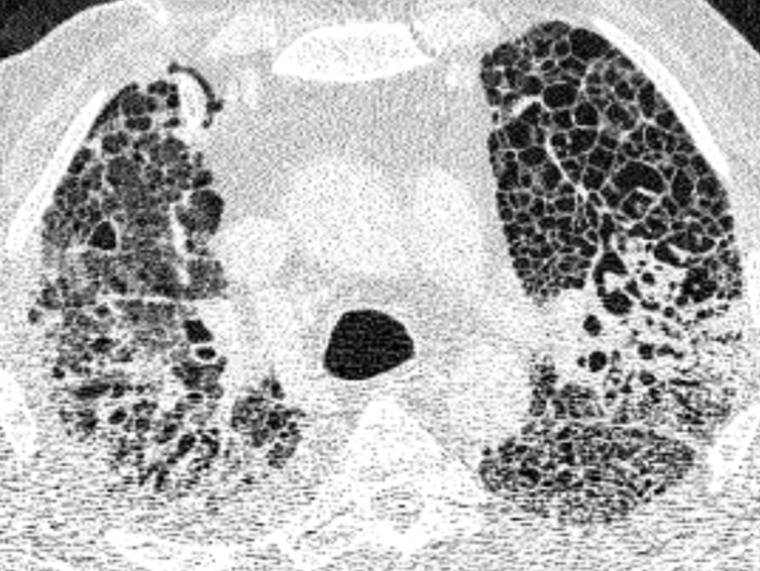

„Unsere Daten zeigen also eindeutig Parallelen zwischen COVID-19 und der chronischen Lungenfibrose auf“, resümiert Dr. Saliba. „Das erklärt vielleicht, warum einige Risikofaktoren für COVID-19 auch Risikofaktoren für die idiopathische Lungenfibrose sind – z.B. Grunderkrankungen, Rauchen, ein männliches Geschlecht und ein Alter über 60 Jahre. Es gibt jedoch einen entscheidenden Unterschied zwischen den beiden Erkrankungen: Bei COVID-19 ist die Vernarbung zumindest potenziell reparabel.“ Das konnte das Forschungsteam anhand von CT-Bildern nachvollziehen. Bei COVID-19-Erkrankten, die mit der ECMO behandelt wurden, zeigten die Aufnahmen zunächst typische milchglasartige Trübungen, die sich im Verlauf der Erkrankung verdichteten und vernarbten. Bei Betroffenen, die von der ECMO-Behandlung entwöhnt werden konnten und genasen, gelang es dem Körper, die Verdichtungen allmählich aufzulösen – auch wenn in manchen Fällen deutliche Vernarbungsreste zurückblieben.